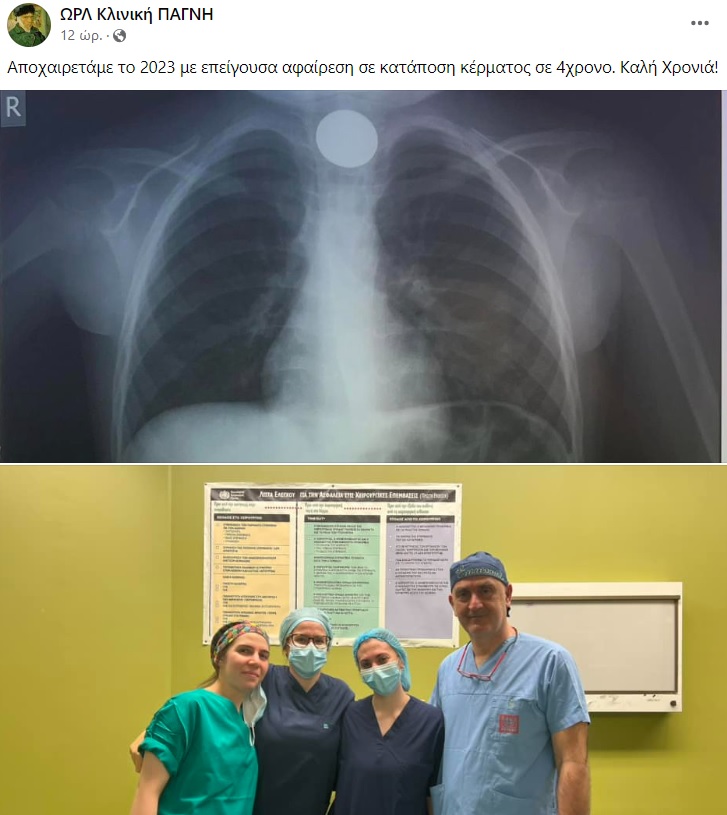

Ηράκλειο: Οι γιατροί προχώρησαν σε επείγουσα αφαίρεση του ξένου σώματος

Εσπευσμένα στο νοσοκομείο μεταφέρθηκε παραμονή Πρωτοχρονιάς ένα παιδί μόλις 4 χρονών.

Όπως αναφέρει το cretapost, το 4χρονο παιδί είχε καταπιεί ένα κέρμα και δεν μπορούσε να αναπνεύσει.

Άμεσα οδηγήθηκε στο ΠΑΓΝΗ με τους γιατρούς να προχωρούν σε επείγουσα αφαίρεση η οποία στέφθηκε με επιτυχία.

Το περιστατικό γνωστοποιήθηκε από την ΩΡΛ κλινική του νοσοκομείου μέσω ανάρτησης στα social media: